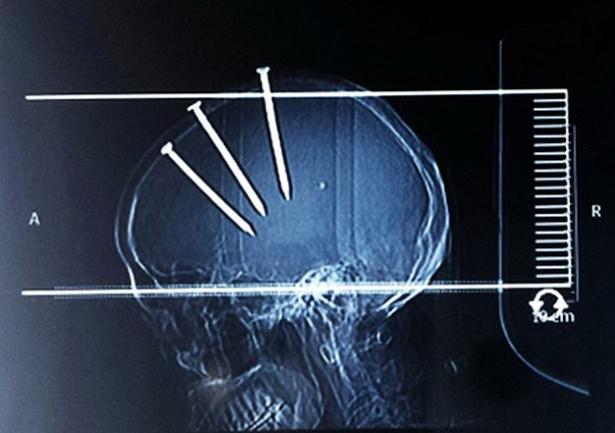

Çivilerin başları açıkça dışarıdan bile görünürken doktorlar Çinli adamın röntgenini çekti ve 3 koca çivi ile karşılaştı...